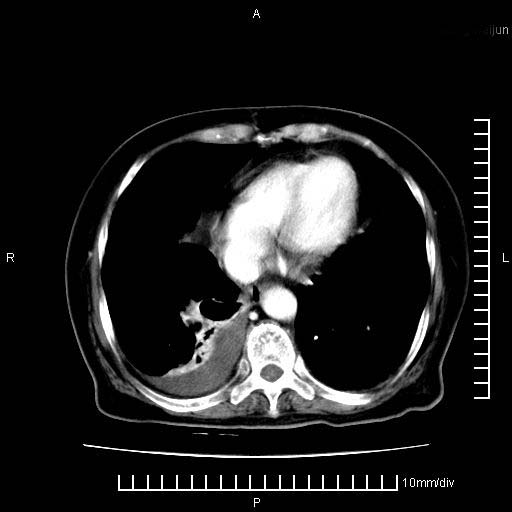

标题: CT28280:腹部增强:女性,80岁

上腹疼痛月余,外院核磁诊断胰腺癌。现临床示右下腹可明显触及包块,可片子上怎么没有看到?

1.胰腺颈体部癌。

2。腹腔积液。

3。右胸腔积液,伴右肺下叶部分萎陷。

4。右肾盂囊肿。